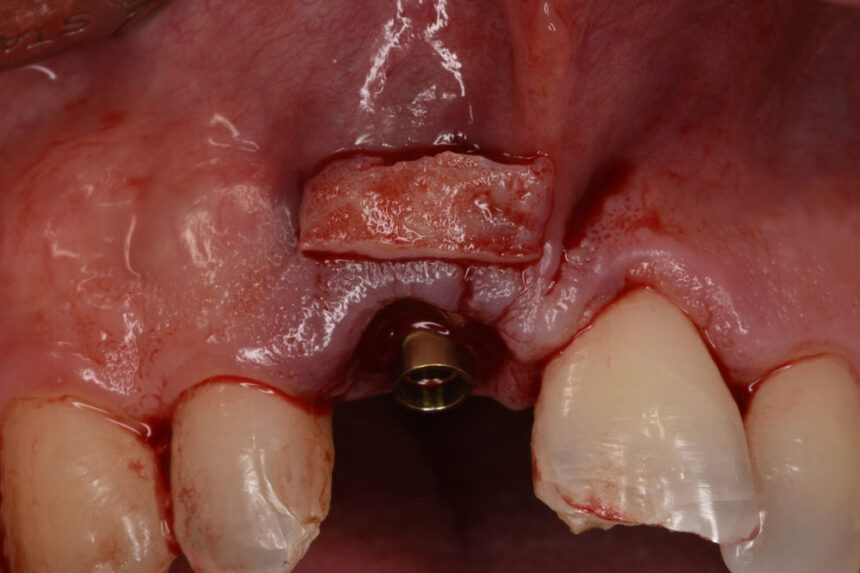

Άμεση κατευθυνόμενη τοποθέτηση εμφυτεύματος σε μετεξακτικό φατνίο στην αισθητική ζώνη. Θεραπευτικές προσεγγίσεις από το βιολογικό υπόβαθρο στο live surgery.

Στο περιστατικό που θα αντιμετωπιστεί live θα γίνει άμεση τοποθέτηση εμφυτεύματος με πλήρη καθοδήγηση χειρουργικού νάρθηκα, θα συζητηθούν οι εναλλακτικές προσεγγίσεις και θα παρουσιαστεί ο τρόπος και τα διαφορετικά σενάρια εξατομίκευσης της επούλωσης των μαλακών ιστών.

- Τοποθέτηση οστικού μοσχεύματος

- Τεχνικές λήψης μοσχεύματος συνδετικού ιστού και για αύξηση του όγκου των προστομιακών ούλων

- Τεχνικές συρραφής για μυλική μεατόπιση κρημνού και σταθεροποίηση μοσχεύματος μαλακών ιστών

- Διαμόρφωση εξατομικευμένου προσθετικού προφίλ ανάδυσης